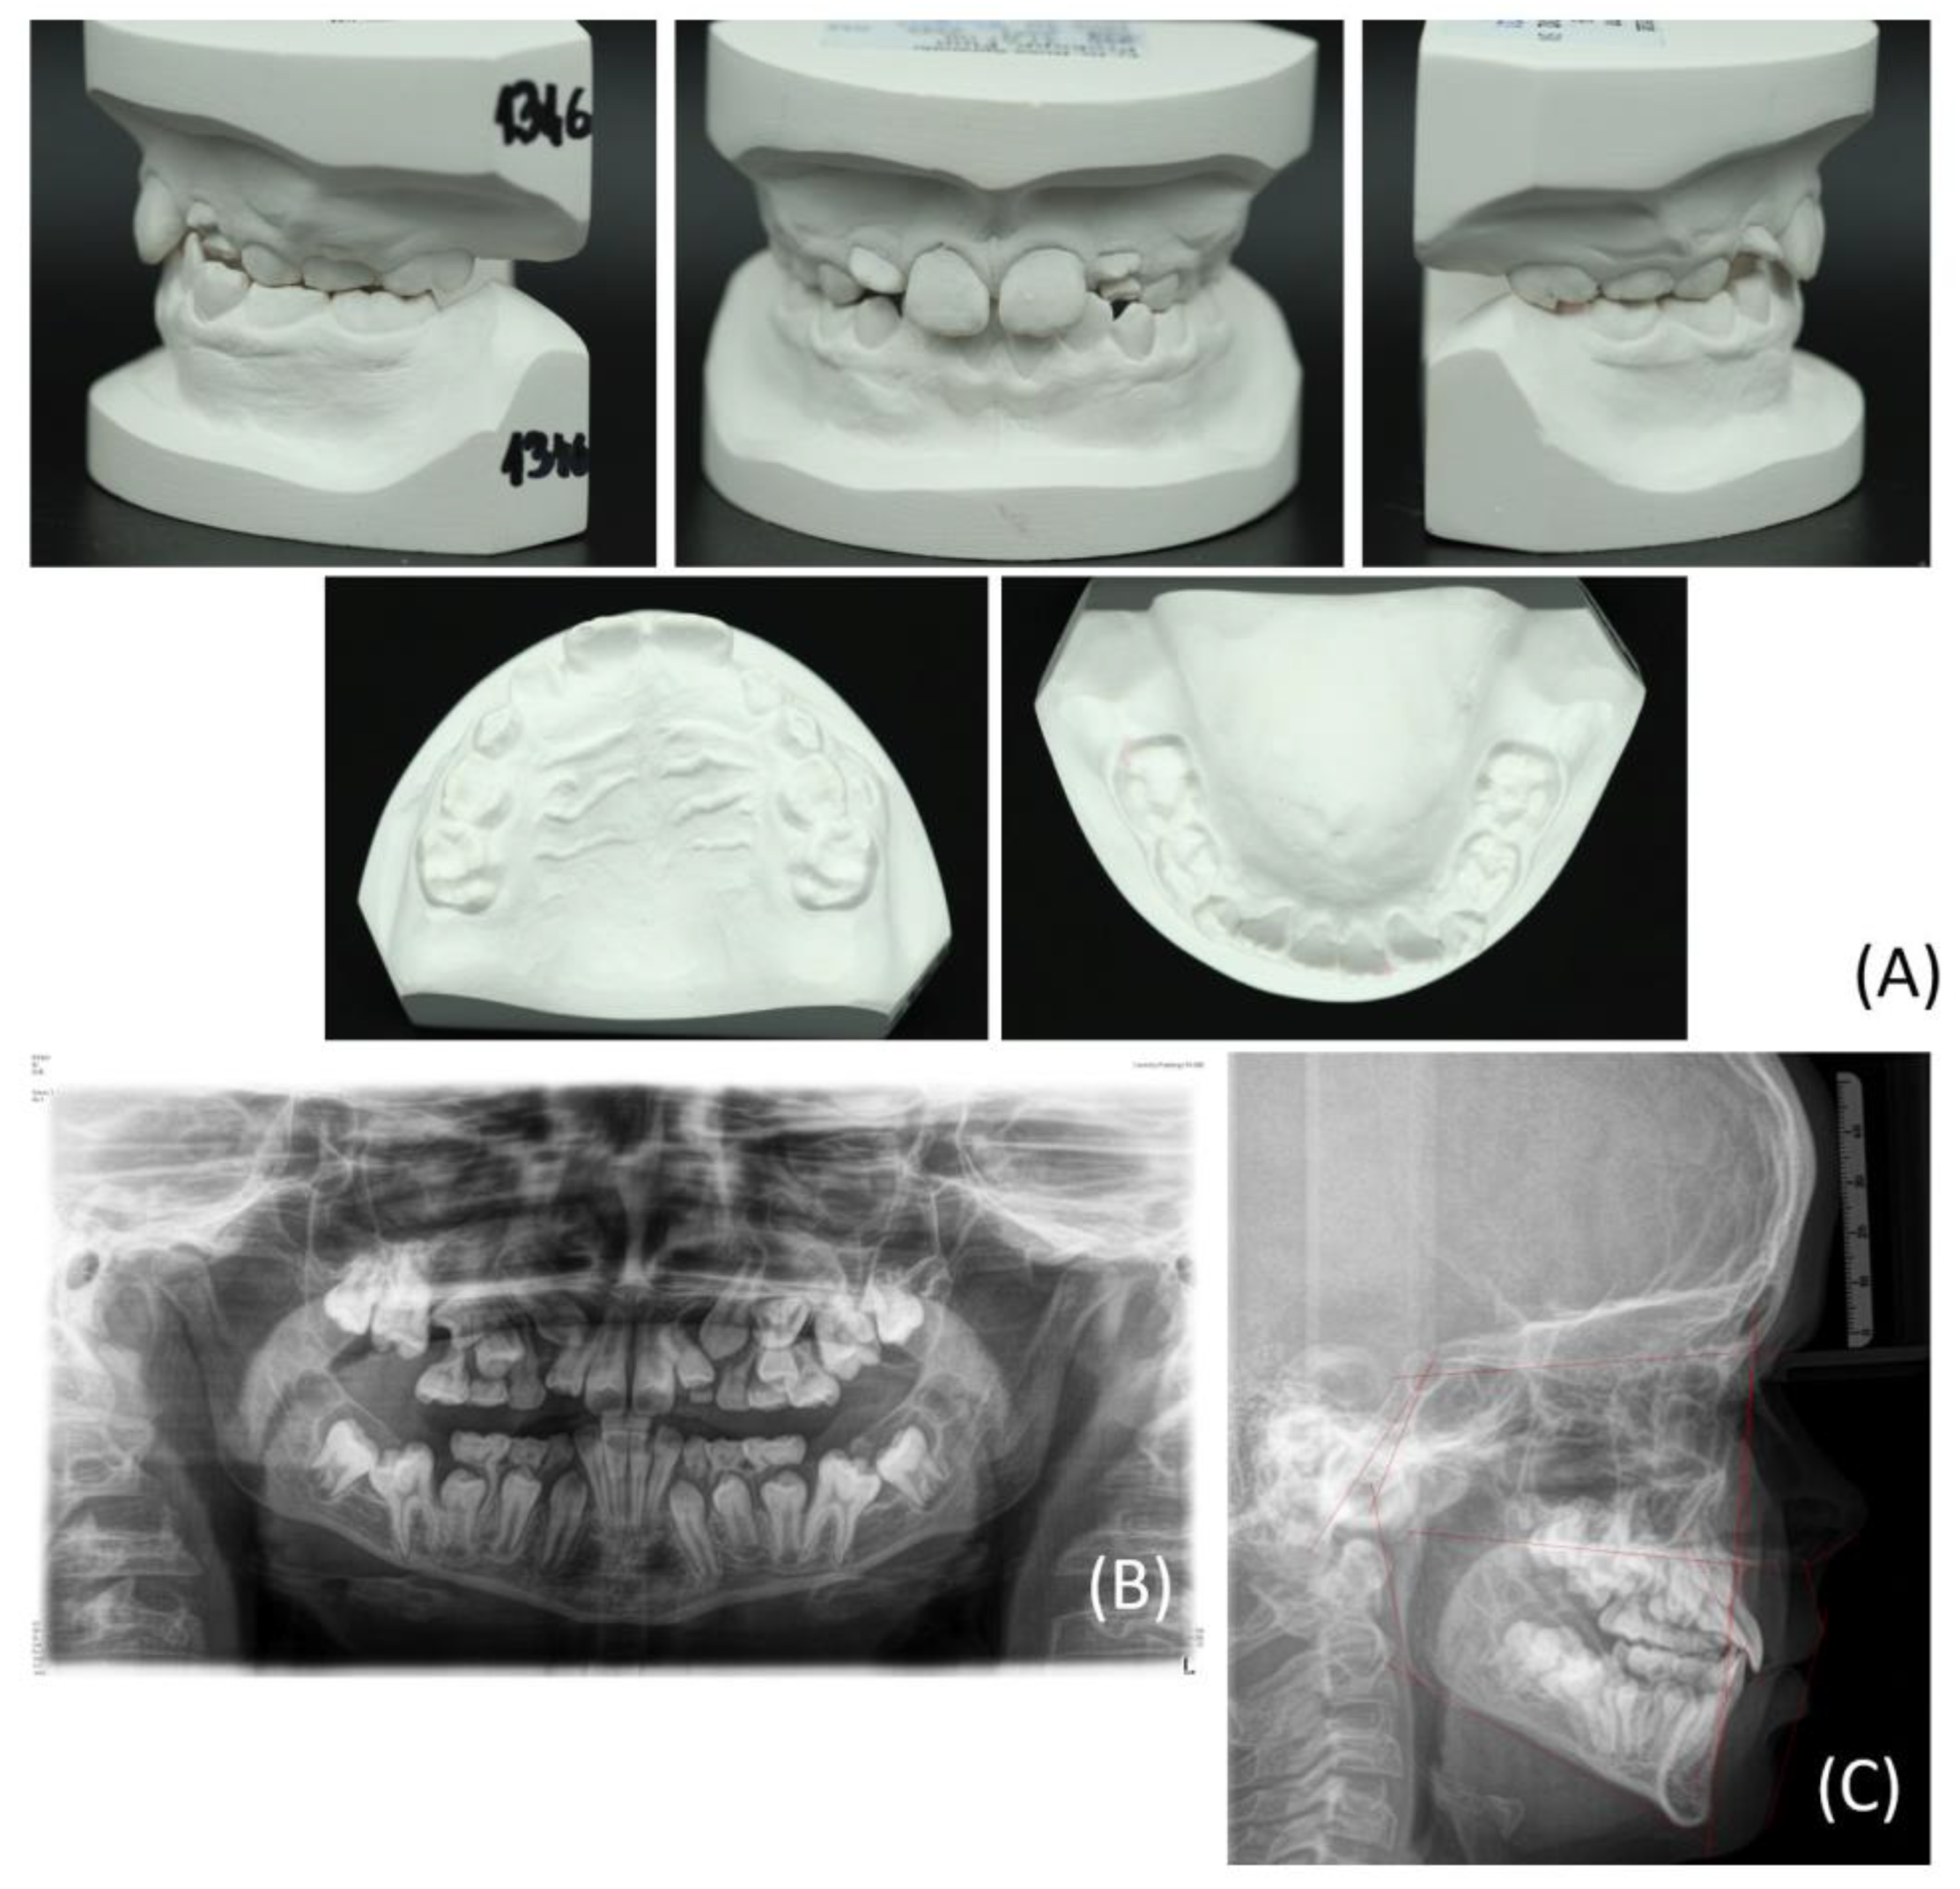

2. Clinical Example Presentation

2.1. Patient Case

2.2. Treatment Methods and Objectives